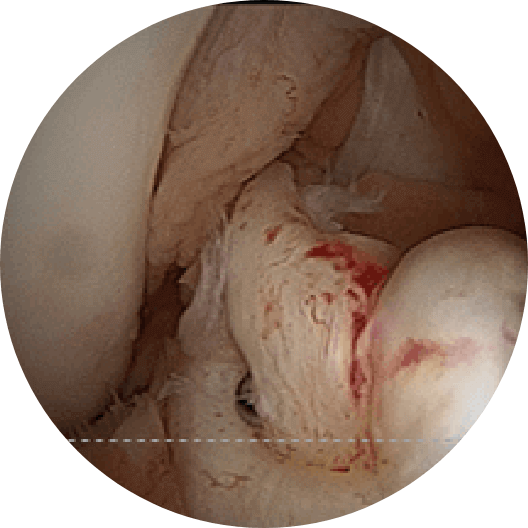

癒合した半月板損傷部

半月板は膝関節の大腿骨と脛骨の間にあり、クッションのような働きと膝を安定化させる機能があります。 半月板が損傷すると、膝の曲げ伸ばしの際に痛みや引っかかりを感じます。またひどい場合には半月板が嵌頓し、膝が動かせなくなるロッキングという状態となり、歩けないほど痛くなることがあります。原因はスポーツなどのケガによって生じる場合と、加齢によって痛む場合があります。また前述の前十字靭帯損傷に合併して起こるものもあります。

治療法は、リハビリや保存的治療で改善する場合も多いですが、症状が改善しない場合やロッキングなど症状が強い場合は手術が勧められます。手術は、関節鏡を使った関節鏡下手術を行います。切除術と縫合術がありますが、当科ではできる限り半月板機能を温存するため縫合術を積極的に行っています。 -